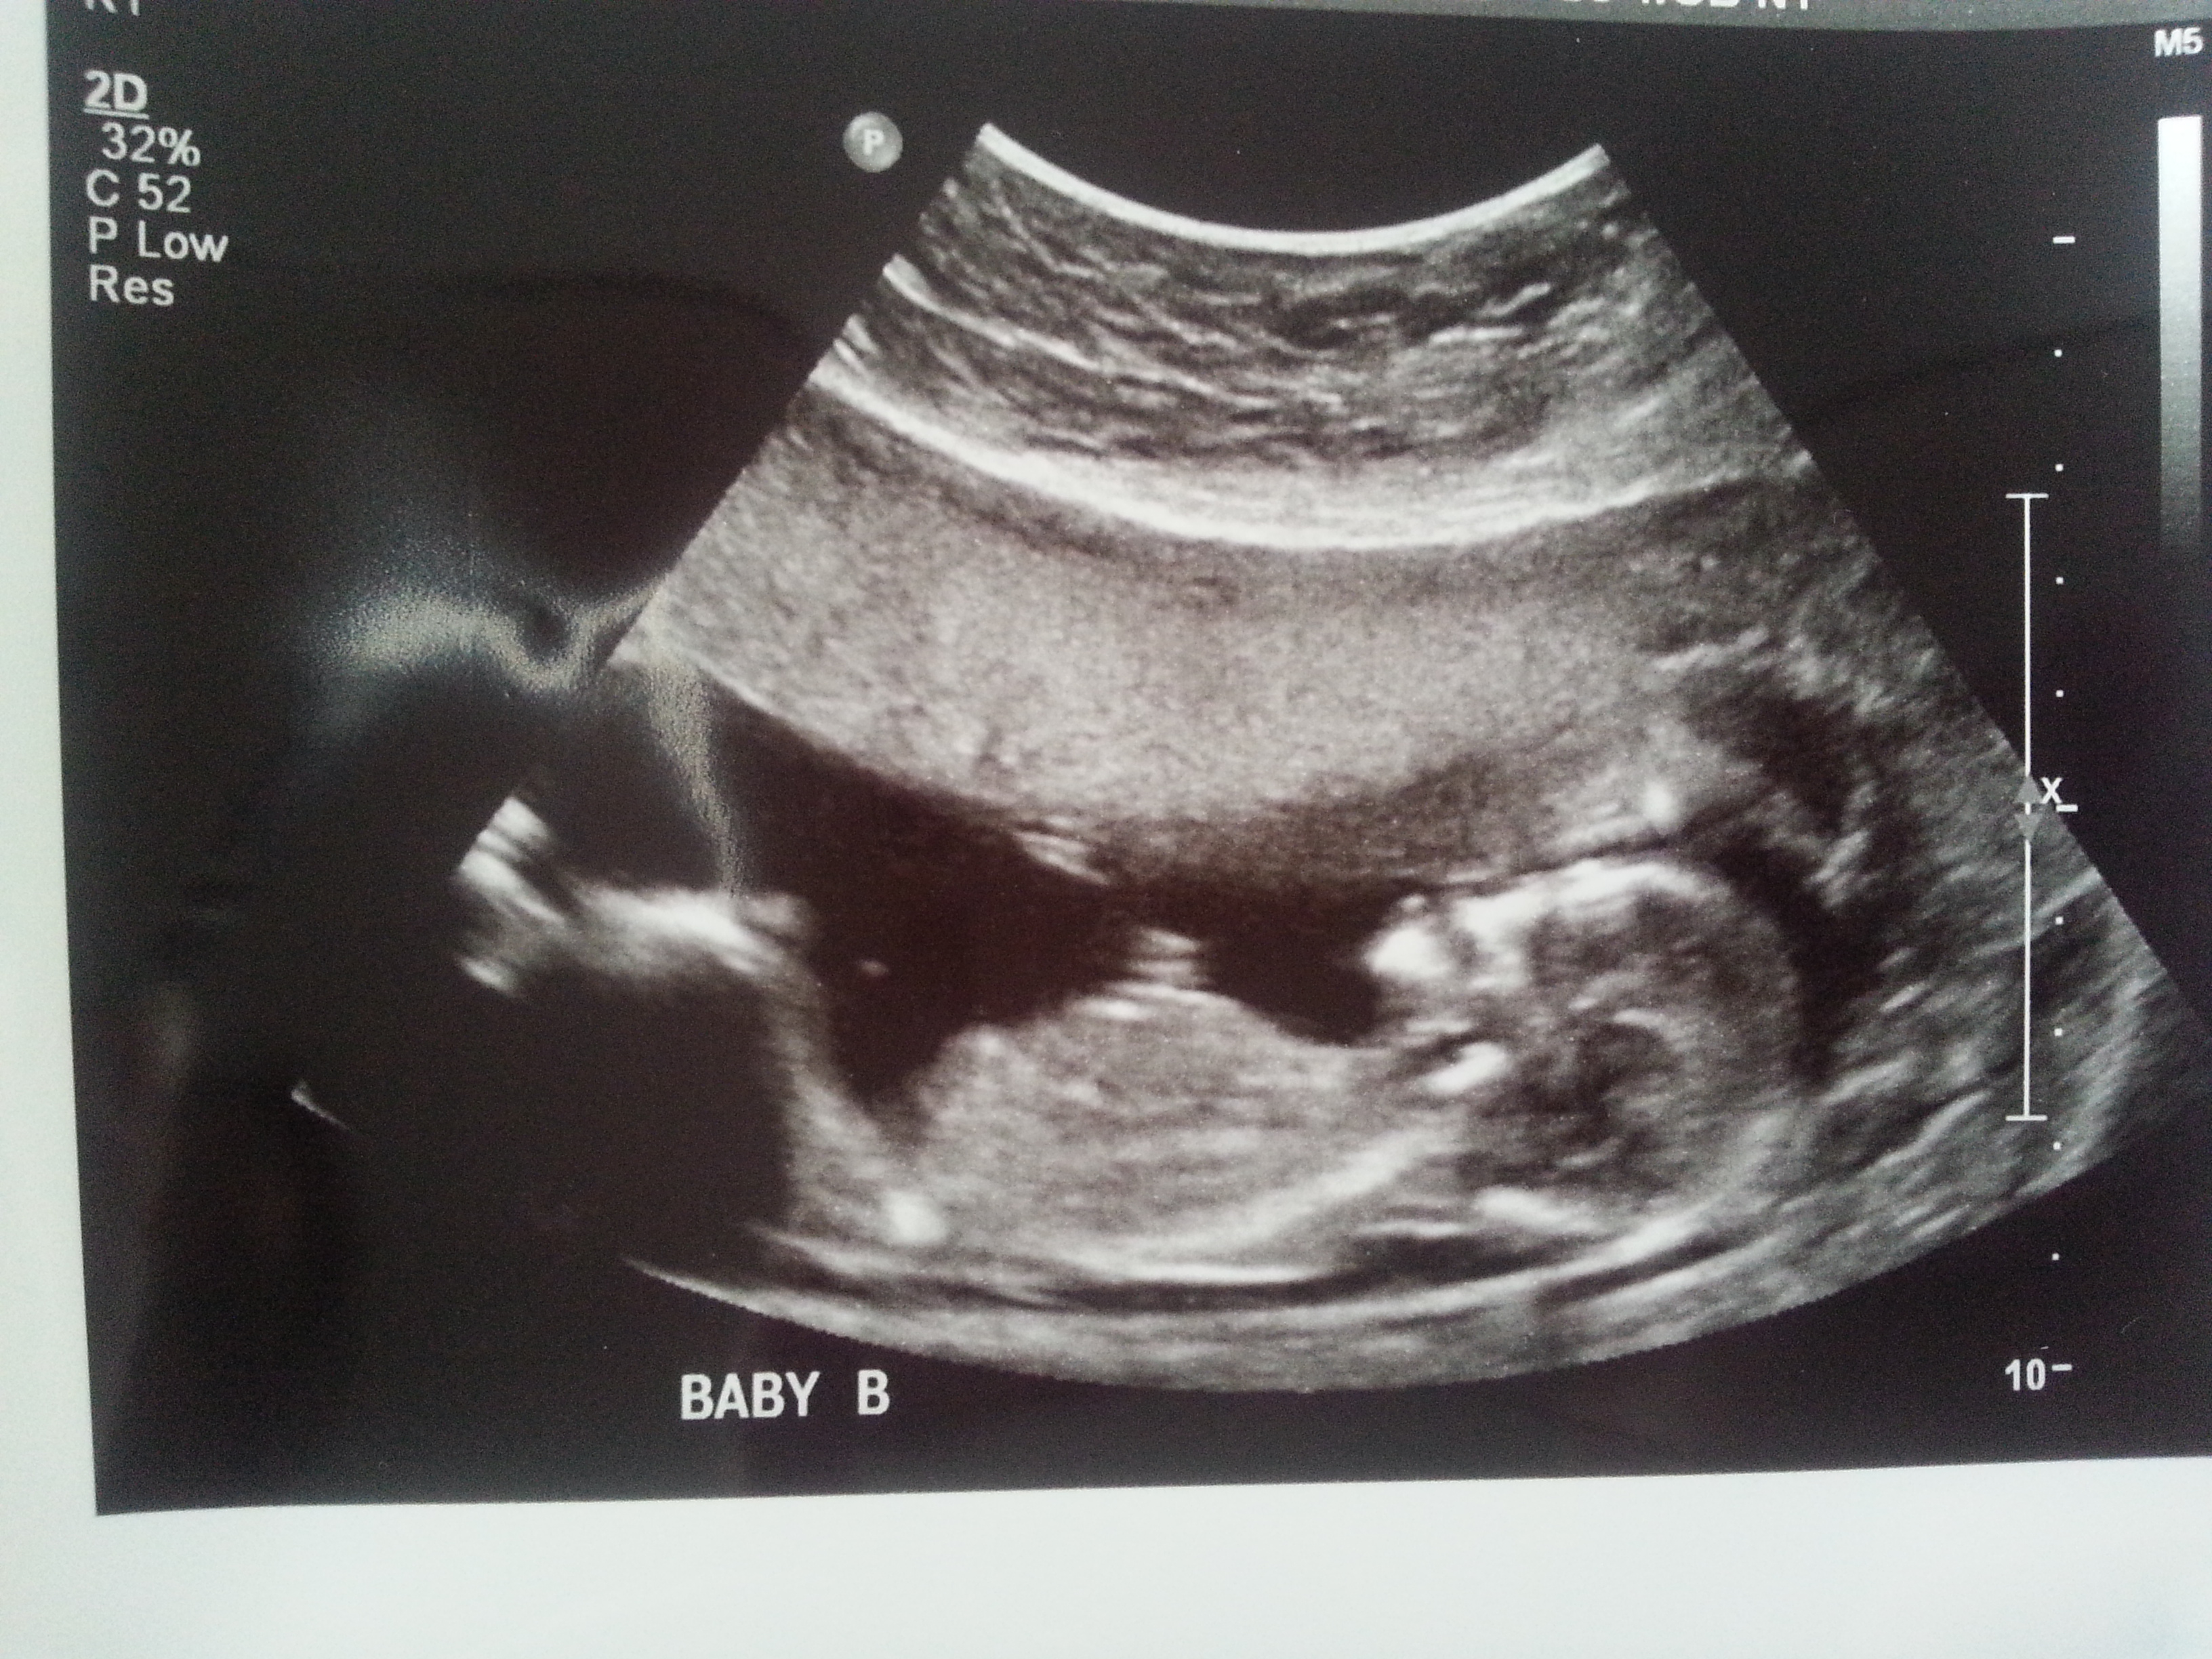

I was 12weeks 6 days and measuring 13weeks 3 days.

Attachment 23436

I think B is a boy and A is a girl.

I think B is a boy, A could go either way but I lean boy.

I think I'm seeing a very boyish nub for baby B. Baby A not as sure. I hope that's your girl! Congrats and good luck!

On your second pic of baby B I'm looking at the little line between the legs that's almost sticking straight up.... very boyish "angle of the dangle".

I'd guess boy/girl too. Baby B looks really boyish. Baby A is more questionable, but at 13 weeks, I'll lean girl.

I think B is def a boy. A has a boyish skull but girly nub. I'd go with the nub though and lean girl! Congrats on your twins!